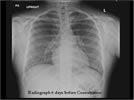

There is obliteration of the right costo-phrenic angle and obscured right diaphragm. The right lateral decubitus view shows a shiftining fluid level indicating free fluid above the right hemidiaphragm

When further history was obtained, we found out that 10 days prior to the current ED presentation, she had an upper respiratory tract infection and 4 days after that she had a syncopal episode at school. That happened during exercise, and during that episode she was noticed to be pale. It lasted only one minute. She lost bowel control during that episode, but she recovered without residual symptoms. She was then evaluated at our ED: physical examination was entirely normal, ECG was normal, CT scan with infusion of the head was normal, and ß-HCG was negative. A chest radiograph was done at that time